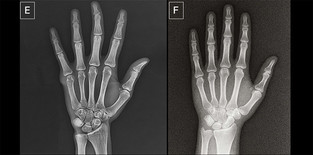

| ▲ 진짜일까요, 가짜일까요? 이 엑스레이 이미지 중 하나는 인공지능이 생성한 것이고, 다른 하나는 실제 이미지다. 어느 것이 진짜일까? (정답은 기사 끝부분에 있다) © Radiological Society of North America (RSNA)

*이미지 설명: 맨 위 사진중, 왼쪽 이미지는 실제이고, 오른쪽 이미지는 GPT-4o로 생성된 이미지다